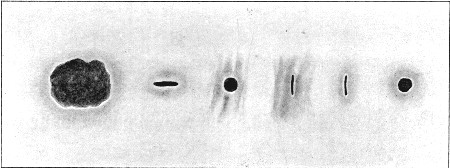

22. Entry and Exit Wounds in Six Successive Spots made by same Bullet61

23. Four Successive Entry and Exit Wounds of same Bullet62